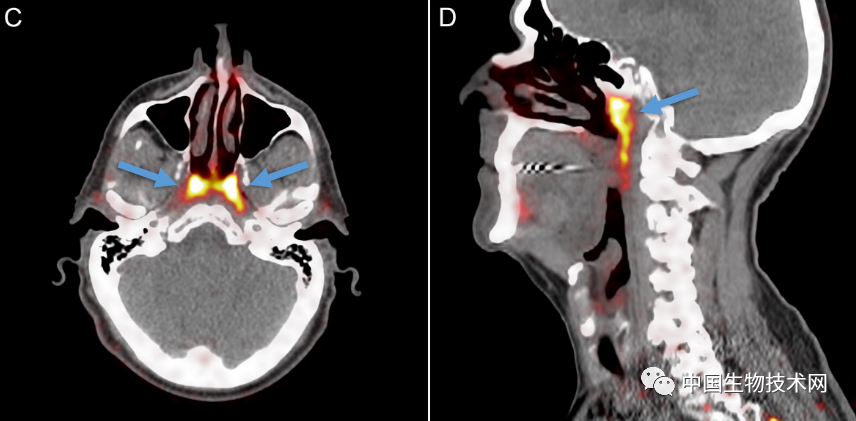

Vogel团队新发现的要大得多,它显示出似乎是先前被忽视的一对腺体,表面上看是第四大主要唾液腺,位于鼻咽后部、上颚上方,靠近人类头部的中心。

该研究第一作者,阿姆斯特丹大学的口腔外科医生Matthijs Valstar说:“这两个新发现的区域也具有唾液腺的其他特征。根据它们的解剖位置(在咽鼓管上方),我们称之为‘管状腺’(tubarial glands)。”

在对所有100例患者进行的PSMA PET/CT扫描,均发现存在这些管腺,并且对两名尸体(一男一女)的身体检查也显示出神秘的双侧结构,从宏观上可见引流管开口朝向鼻咽壁。

至于这些腺体是如何被识别出来的,研究人员表示,“管状腺”是在颅底一个不易接近的解剖位置被发现的,用内窥镜是很难辨认出来的,因为它们是一个更大腺体系统的一部分。此外,只有更新的PSMA-PET/CT成像技术才能检测到新唾液腺的结构,这超出了超声波、CT和MRI扫描等技术的可视化能力。